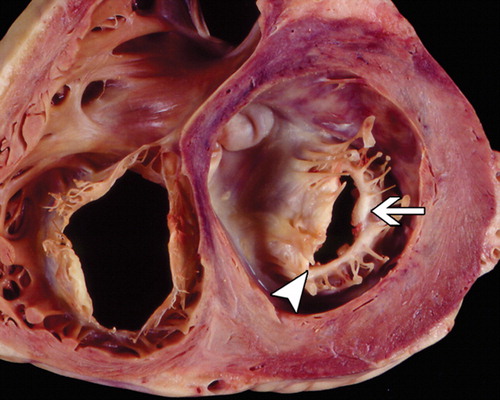

مهم ترین بیماری های دریچه میترال مربوط به عملکرد دریچه است که مانع بسته شدن یا باز شدن نرمال دریچه می شوند. تنگی دریچه میترال باعث تجمع خون در پشت دریچه می شود و نارسایی کلیه موجب پس زدن خون از بطن چپ به داخل دهلیز چپ می شود.

در کنار تنگی و نارسایی دریچه میترال ، پرولاپس دریچه میترال هم وجود دارد که علیرغم خطر بسیار اندک ، سر و صدا و علایم زیادی دارد.